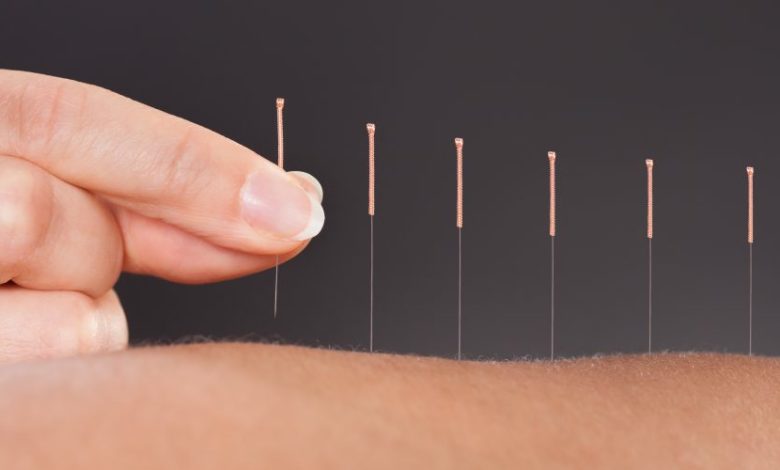

Devamını Oku »Akupunktur, tıpta birçok alanda etkili olmakla beraber, en kesin ve yüzgüldürücü etkiler migren hastalarında görülmektedir. Uzm. Dr. Evren Kul Panza Başağrılarına…

Devamını Oku »Kuru iğne tedavisi, farklı uzunluklardaki çok ince akupunktur iğnesinin kas başta olmak üzere yumuşak dokulara batırılarak yapılan tedavi yöntemidir. Kuru…